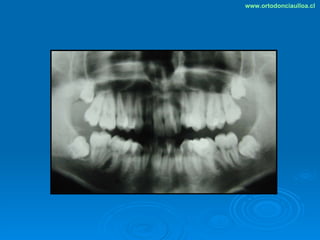

Este documento presenta dos casos clínicos de pacientes que recibieron tratamiento de ortodoncia. El primer caso fue de una paciente femenina de 14 años con apiñamiento dental y mordida cruzada que fue tratada mediante extracción de premolares y alineamiento dental. El segundo caso fue de un paciente masculino de 14 años con clase II esqueletal y desarmonía dentomaxilar que fue tratado con extracción de premolares y corrección de mordida. Ambos casos mostraron mejoría después de 3 años de tratamiento.